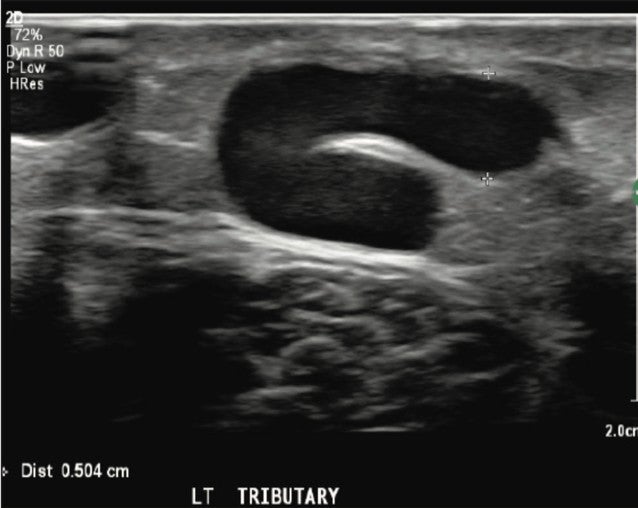

Upon completion of venous Doppler reflux ultrasound, multiple large caliber saphenous tributary varicose veins and remnants of the previously treated Great Saphenous Vein (GSV) were demonstrated at proximal thigh.

A GSV reflux pattern was observed at the thigh level and extended distally. Vein diameters ranged from 4.7-5 .1mm in the largest associated GSV tributary vein. Reflux times ranged from 2-3.2 seconds.

Figure 1. Left GSV tributary vein prior to Varithena treatment.